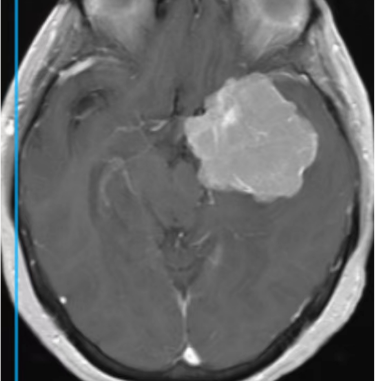

蝶骨嵴脑膜瘤是脑膜瘤的一种类型,属于颅底脑膜瘤,即前中颅底交界处蝶骨嵴部位的硬膜生长出的肿瘤,分为蝶骨嵴外侧部(大翼部)、中部(小翼部)和内侧部(床突部)3个亚型,可以影响血管,对静脉产生挤压,形成局部脑水肿。 大型蝶骨嵴脑膜瘤可包绕颈内动脉或压迫大脑后动脉引起患者眩晕,呈短暂性脑缺血发作,也可表现为脑梗死。蝶骨嵴中外侧的脑膜瘤以头痛和颅高压常见,患者可有癫痫、失语、对侧肢体无力等症状。蝶骨嵴内侧型脑膜瘤生长于前床突或蝶骨嵴内侧,患者可出现视野缺损、单眼视力障碍等视神经损伤症状。 蝶骨嵴脑膜瘤建议手术切除治疗,对于手术切除有难度的患者,手术后有残留肿瘤的患者可以选择放射治疗。